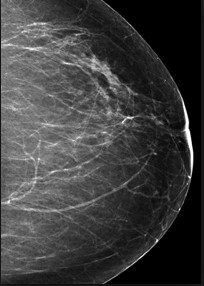

Pandangan Mamografi

Ini melibatkan pengambilan rontgen payudara dalam 2 tampilan setiap tahun atau dua tahun sekali mengikuti pedoman yang direkomendasikan.

- Tampilan MLO (medial lateral oblique view)

- Tampilan CC (cranial-caudal view)

MMG – pandangan MLO MMG – pandangan CC

MMG – pandangan CC MMG –pandangan MLO